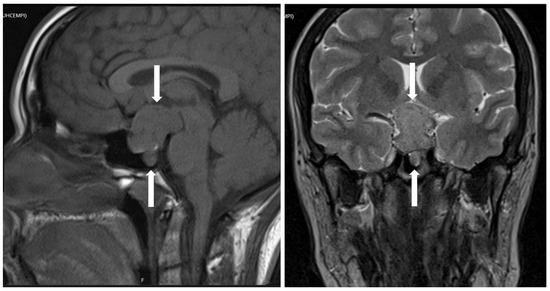

- Asa, S.L.; Kucharczyk, W.; Ezzat, S. Pituitary acromegaly: Not one disease. Endocr. Relat. Cancer 2017, 24, C1–C4. [Google Scholar] [CrossRef] [PubMed]